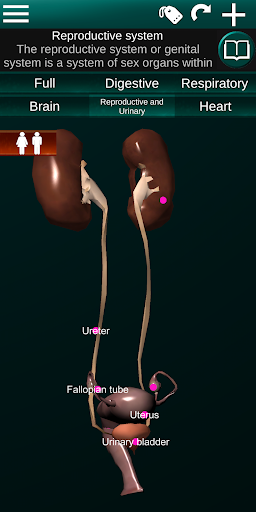

Toont een 3D-anatomisch model van de belangrijkste organen van het menselijk lichaam en een beschrijving van elk orgaan.

* Voortplantingssysteem, dat de mannelijke en vrouwelijke voortplantingsorganen omvat.

* Vergelijk mannelijke en vrouwelijke organen.